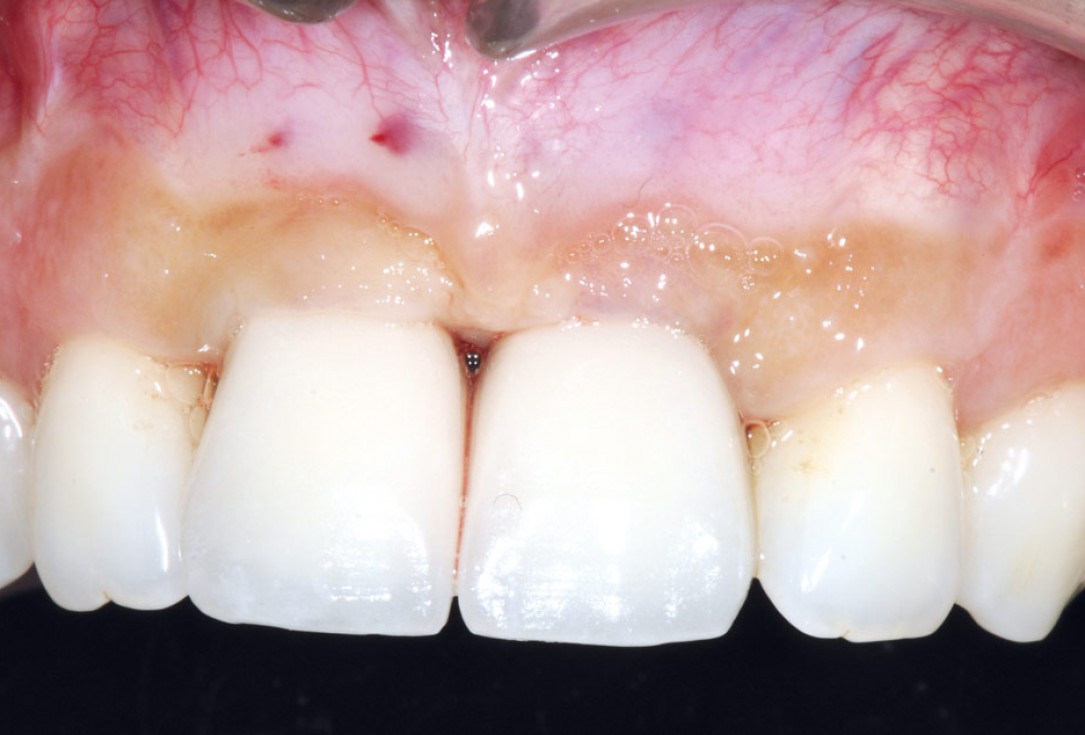

25/26 - Final crowns immediatly after restorationBone augmentation in aesthetic zone with maxgraft® bonering - Dr. A. Patel